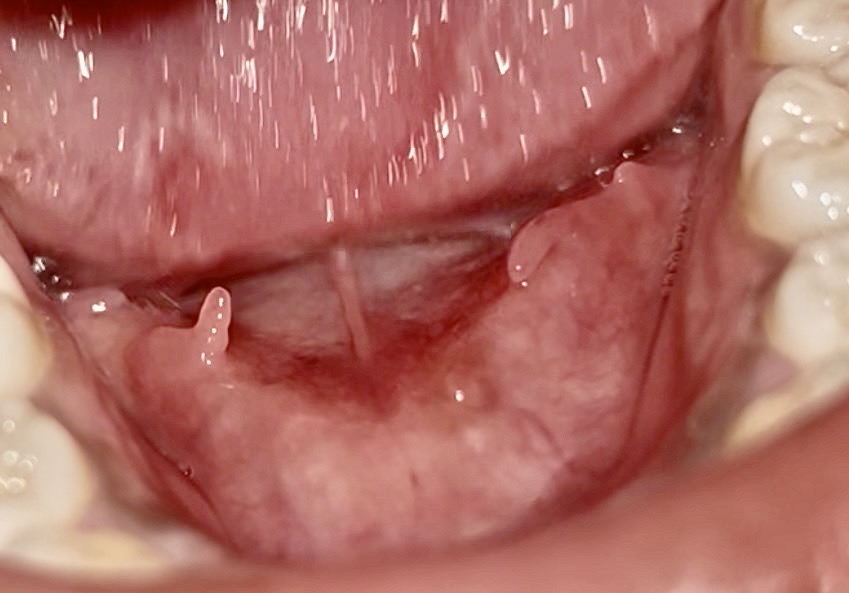

20 มีนาคม 2569 11:46:27 #1 มันคืออะไรคะ ไม่มีอาการเจ็บ https://haamor.com/media/create_topic/20260320113343.jpeg

23 มีนาคม 2569 12:50:52 #2 จากรูปภาพที่คุณส่งมา ติ่งเนื้อลักษณะนี้ที่อยู่บริ ข้อมูลเบื้องต้นเกี่ยวกับ Plica Fimbriata • มันคืออะไร: เป็นเนื้อเยื่อที่มีลักษณะเป็ • อันตรายไหม: โดยปกติแล้ว ไม่มีอันตรายครับ ไม่ใช่โรค ไม่ใช่การติดเชื้อ และไม่ใช่เนื้อร้าย • ทำไมถึงเพิ่งเห็น: บางคนอาจจะมีติ่งนี้ชัดเจนกว่ เมื่อไหร่ที่ควรไปพบแพทย์ แม้ว่าส่วนใหญ่จะเป็นเรื่องปกติ แต่ควรสังเกตอาการเพิ่มเติม หากมีลักษณะดังนี้ควรไปปรึกษาทั 1. ติ่งเนื้อมีขนาดใหญ่ขึ้นอย่ 2. สีเปลี่ยนไป (เช่น กลายเป็นสีขาวจัด แดงจัด หรือดำ) 3. เริ่มมีอาการเจ็บ ปวด หรือมีเลือดออก 4. มีลักษณะแข็งเป็นก้อน สรุป: หากไม่มีอาการเจ็บและลักษณะเหมื |